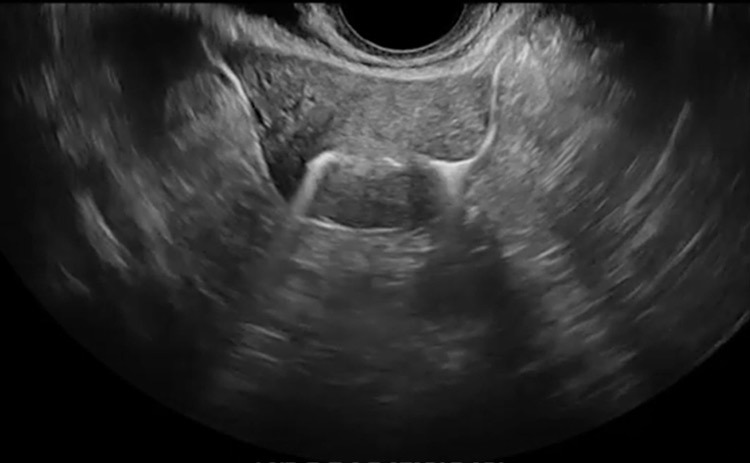

Παράδειγμα Υπερηχογραφικής σαλπιγγογραφίας HYFOSY βέλος : όπου φαίνεται διαπερατότητα, υπερηχογενές σκιαγραφικό στην αριστερή σάλπιγγα με ροή

Παράδειγμα Υπερηχογραφικής σαλπιγγογραφίας HYFOSY με τρισδιάστατη απεικόνιση ενδομητρικής κοιλότητας και σαλπιγγικής διαπερατότητας